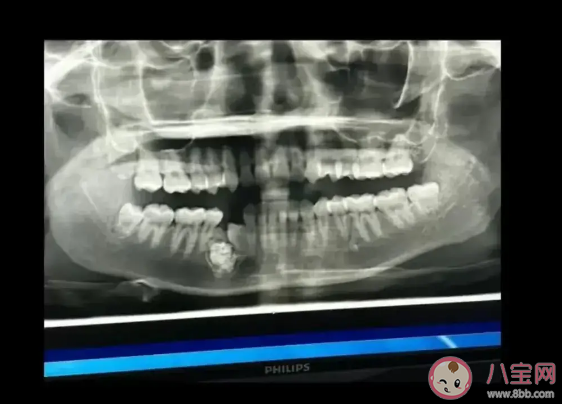

牙瘤是一种常见的口腔疾病,通常是指在牙床内生长的异常牙齿或牙组织。牙瘤虽然名为瘤,但并非真正的肿瘤,一般不会引起癌变。牙瘤内含有不同发育阶段的各种牙胚组织或牙,数个至数十个不等,形状不规则,有的近似正常牙,有的只是一团紊乱的硬组织。

牙瘤是由釉质、牙本质、牙骨质和牙髓组织构成的,一般可以分为两种类型:第一种是混合性牙瘤,构成牙齿的四种组织混杂存在,形成不规则的坚硬肿瘤团块,没有完整的牙齿形成。第二个是组合牙瘤,构成牙齿的四种组织按正常牙齿相似排列,形成大小不一、形态各异的牙齿,数目少则数个,多则可达百余个,聚集成一团块。如果发现长有牙瘤,建议及时前往医院口腔科就诊。